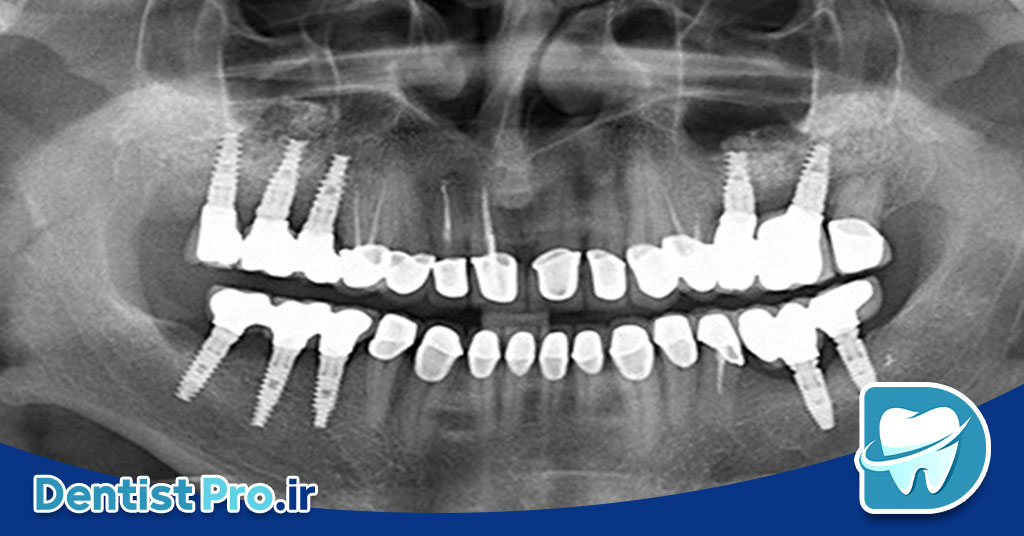

اندودنتیکس سه بعدی با تصویربرداری CBCT به معنای استفاده از اسکنر CBCT برای تهیه تصاویر سهبعدی از دندان، کانالهای ریشه، استخوان اطراف و ساختارهای پیرامونی است تا تصمیمگیری دقیقتری برای درمان ریشه انجام شود.

CBCT یک تکنولوژی تصویربرداری با اشعه ایکس است که برخلاف رادیوگرافیهای سنتی، تصویری حجمی و دقیق از منطقه مورد نظر فراهم میکند. در اندودنتیکس، این مزیت باعث میشود جزئیات کانالهای فرعی، شکستگیهای ریشه، ضایعات پریآپیکال و آناتومی غیرعادی به وضوح دیده شود.